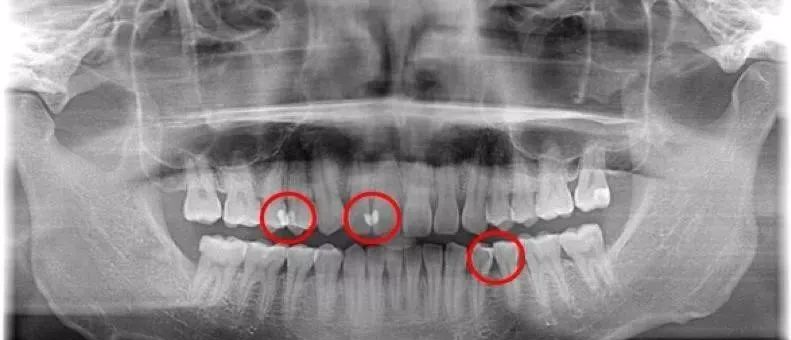

只係口腔清潔呢項細事

大部份人都冇做好